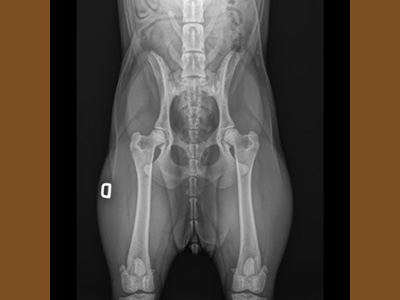

La displasia dell’anca e del gomito è una delle problematiche più conosciute nei cani di taglia grande dove il peso ed il rapido accrescimento evidentemente sono un'aggravante. Vi sono anche altri fattori che possono contribuire ed incidere sulla gravità ma alla base c'è...